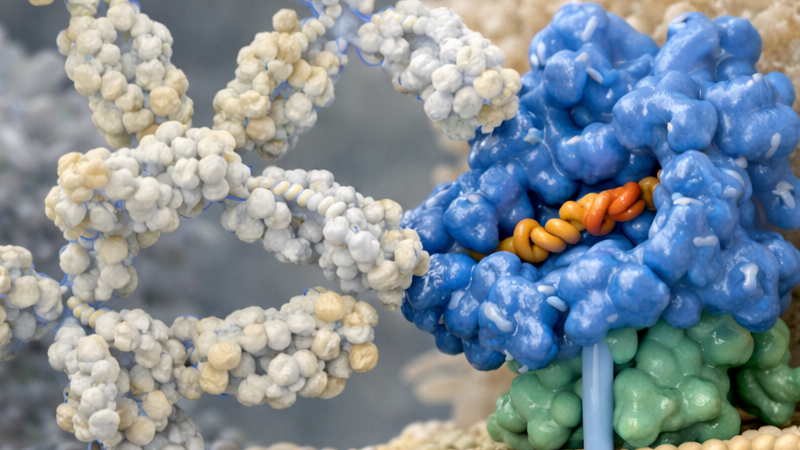

NGS

El término secuenciación de nueva generación (NGS) hace referencia ...